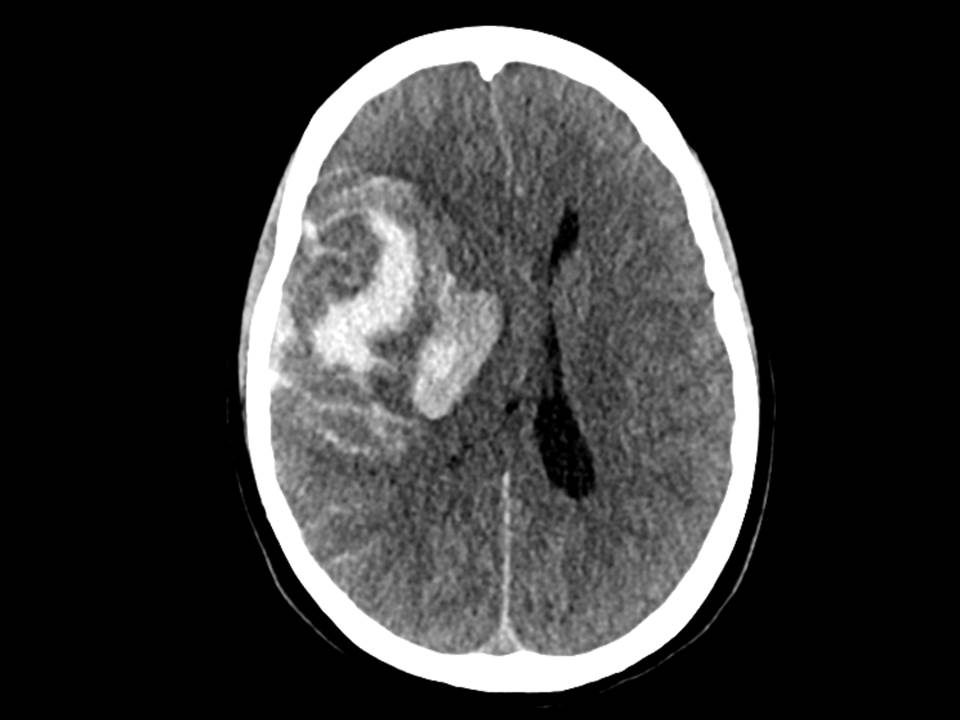

Det var sterk mistanke om intracerebral blødning, og slagalarmen ble utløst. CT caput ble rekvirert og viste en stor høyresidig intracerebral blødning temporoparietalt i forsyningsområdet til arteria cerebri media, utviklende ødem med overskyting av midtlinjestrukturer og kraftig kompresjon av høyre sideventrikkel. Det var både subaraknoidalt blod og en del ferskt blod i hjerneparenkymet (figur 1), men det var ikke synlig blod i ventrikkelsystemet. CT angiografi var uten funn av aneurisme.

Pasienten ankom universitetssykehuset tre timer etter varsling fra lokalsykehuset. Ved mottak hadde pasienten bilateral mydriasis uten lysreaksjon. Behandling med mannitol ble igangsatt, og CT caput tatt umiddelbart etter ankomst viste progrediering av en stor intrakranial blødning med startende herniering (figur 2). Cerebral angiografi (TCD) var forenlig med opphørt blodsirkulasjon i hjernen, og videre tiltak ble vurdert som uhensiktsmessige.

Få dager etter denne hendelsen ble det meldt fra Rikshospitalet om flere tilfeller av alvorlige blodpropper og blødninger hos pasienter som hadde fått identisk vaksine. Også disse pasientene hadde lave trombocyttall, og i disse tilfellene klarte man å finne en sammenheng mellom hendelsene og vaksinen (1). Tilstanden er etter dette omtalt som vaksineindusert trombotisk trombocytopeni (VITT), som kjennetegnes av lave trombocyttall, trombedannelser og antistoff mot platefaktor 4 (1, 5). I lys av denne kunnskapen ble det gjort nye undersøkelser, og man fant også hos vår pasient tendens til trombedannelse med små tromber i sinus transversus, pannelapper og a. pulmonalis. Det ble også påvist antistoff mot platefaktor 4. Samlet sett er det derfor mye som taler for at dette var et tilfelle av vaksineindusert trombotisk trombocytopeni. Retrospektivt må man spørre seg om blødningen sett på CT representerte et venøst hemoragisk infarkt tilsvarende det som ble sett hos flere pasienter på Rikshospitalet (1), og om blødningskomponenten kan ha vært dominerende som følge av vaksineindusert trombotisk trombocytopeni. Et venøst infarkt kunne kanskje forklare pasientens hodepine.